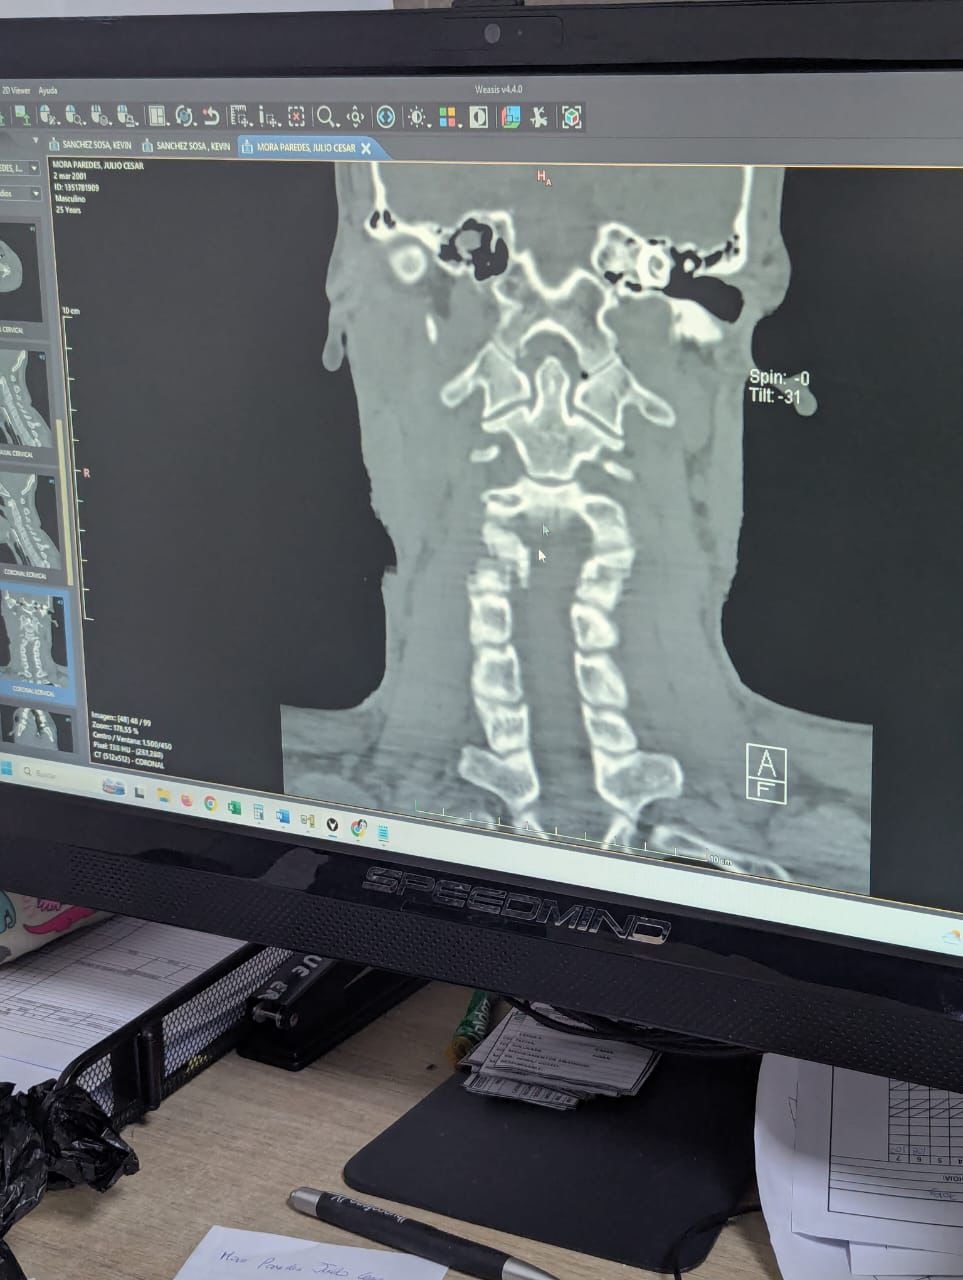

Este Go Fundme fue creado con el propósito de poder ayudar a nuestro querido hermano y amigo Julio César Mora Paredes ( más conocido como Junior ) ya que ha tenido un accidente y su estado es de gravedad, la ayuda será específica para gastos médicos y ayuda en su recuperación, si ya tienes recuerdos con él ,ayuda nuestra causa para su pronta recuperación para poder obtener mas recuerdos con el, al ayudar estamos diciendo Amigo te queremos ver bien y enviamos un abrazo a la distancia.